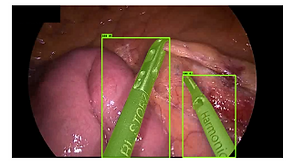

Detection and segmentation of surgical instruments is an important problem for laparoscopic surgery. Accurate pixel-wise instrument segmentation is a useful intermediate task for the development of computer-assisted surgery systems, such as pose estimation, surgical phase estimation, enhanced image fusion, video retrieval and others. In this paper we describe a deep learning-based approach to instrument segmentation, which addresses the binary segmentation problem in which every pixel in an image is labeled as instrument or background. The key novelty of our approach relates to the use of training data which is inexpensive and fast to acquire. First, our approach relies on weak annotations provided as bounding boxes of the instruments, which are much faster and cheaper to obtain than a dense pixel-level annotations. Second, to further improve the system’s accuracy we propose a novel approach to generate synthetic training images. Our approach achieves state-of-the-art results, outperforming previously proposed methods for automatic instrument segmentation, based only on weak annotations.